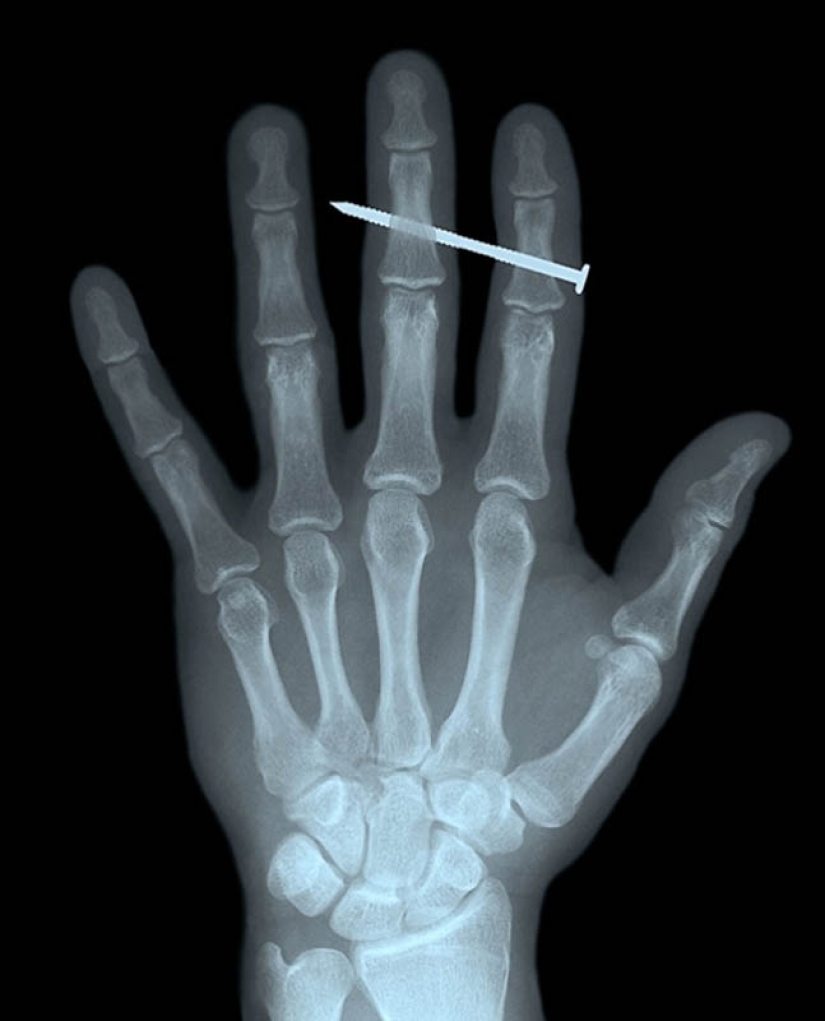

4. Uña en los huesos de los dedos índice y medio de un macho adulto.